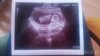

Tu widać siurka , dzidzia ma 5.9cm , z usg 12t3d z om 12t6d .

1490634661-aaaaaa.jpeg

1490634667-aaaaaa.jpeg

Jeeejku jaki Słodziak [emoji7] Gratuluję Synusia w takim razie [emoji16]